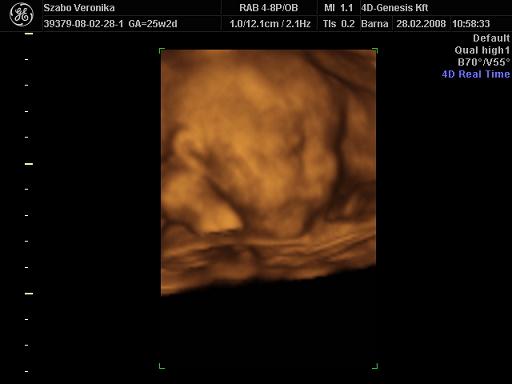

[quote="mpatr"][ írta:mpatrb]Nici, a felvétel élessége és sikerültsége sok mindentől függ.

A profi gépen túl a profi és türelmes szonográfus, a lepény és baba helyzete (mellső fali lepénynél kicsit nehezebb az ügy, meg a babák is imádnak belebújkálni a lepénybe), a magzatvíz mennyisége, a mama hasfalának zsírrétege (mennyire dagi anyuci) szóval ezek (biztos van még) min-mind befolyásolják a felvétel minőségét.

Nekem sikerült ugyanarról a gyerkőcről aki a pocimban van nagyon tuti és nagyon sz..r képet is készíteni ugyanazzal a géppel.

Érdemes többször próbálkozni.